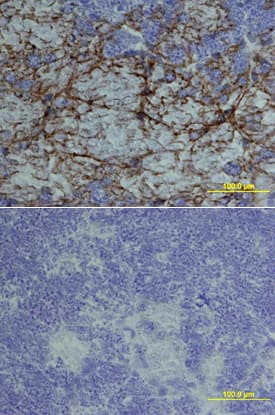

R&D Systems Mouse Artemin Biotinylated Affinity Purified PAb, 50 ug